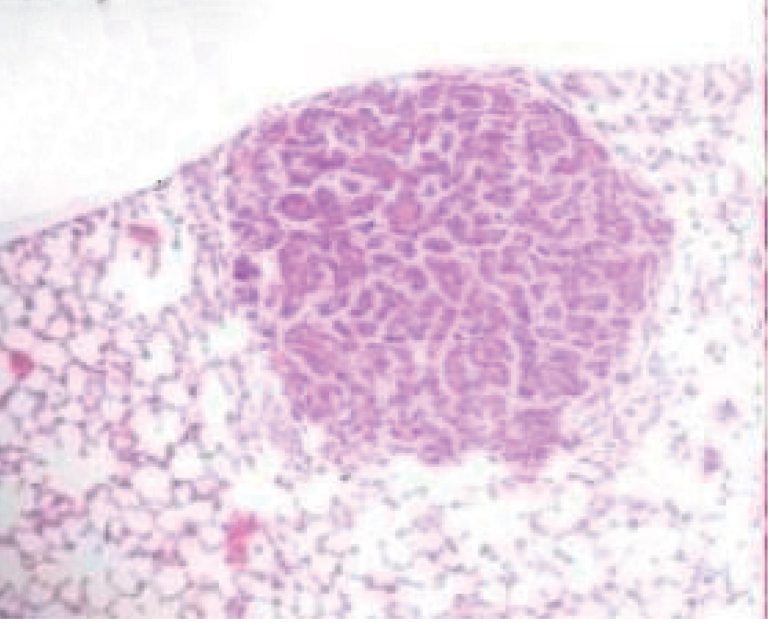

RESUMO Objetivo: Avaliar a ação da janaguba na inibição do desenvolvimento de câncer de pulmão em modelo experimental induzido por uretana. Métodos: Foram injetados 3 mg/kg de uretana em 51 camundongos Balb-C, com 7 a 13 semanas de vida. Janaguba foi administrada via oral diariamente em duas doses: 0,04 mL (Grupo 2, G2) e 0,06 mL (Grupo 3,G3), por 20 semanas. Após esse período, os camundongos foram sacrificados e o número de lesões, contado. Resultados: A média de peso do […]